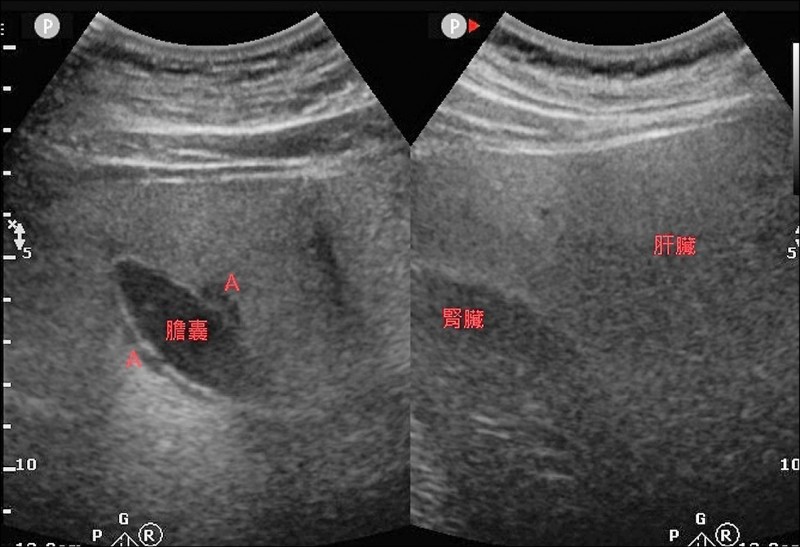

Q:我的先生還是學生的時候,曾抽血發現肝指數過高,當時醫師只說是急性肝炎,因為沒有什麼症狀,他也沒特別理會。後來就自己好了,之後也未再追蹤,最近我跟他一起去體檢,他的肝指數又是紅字,GOT:88、GPT:96,腹部超音波有膽息肉跟重度脂肪肝,請問肝指數高跟以上兩個原因有關嗎?我的先生沒有B、C肝,也